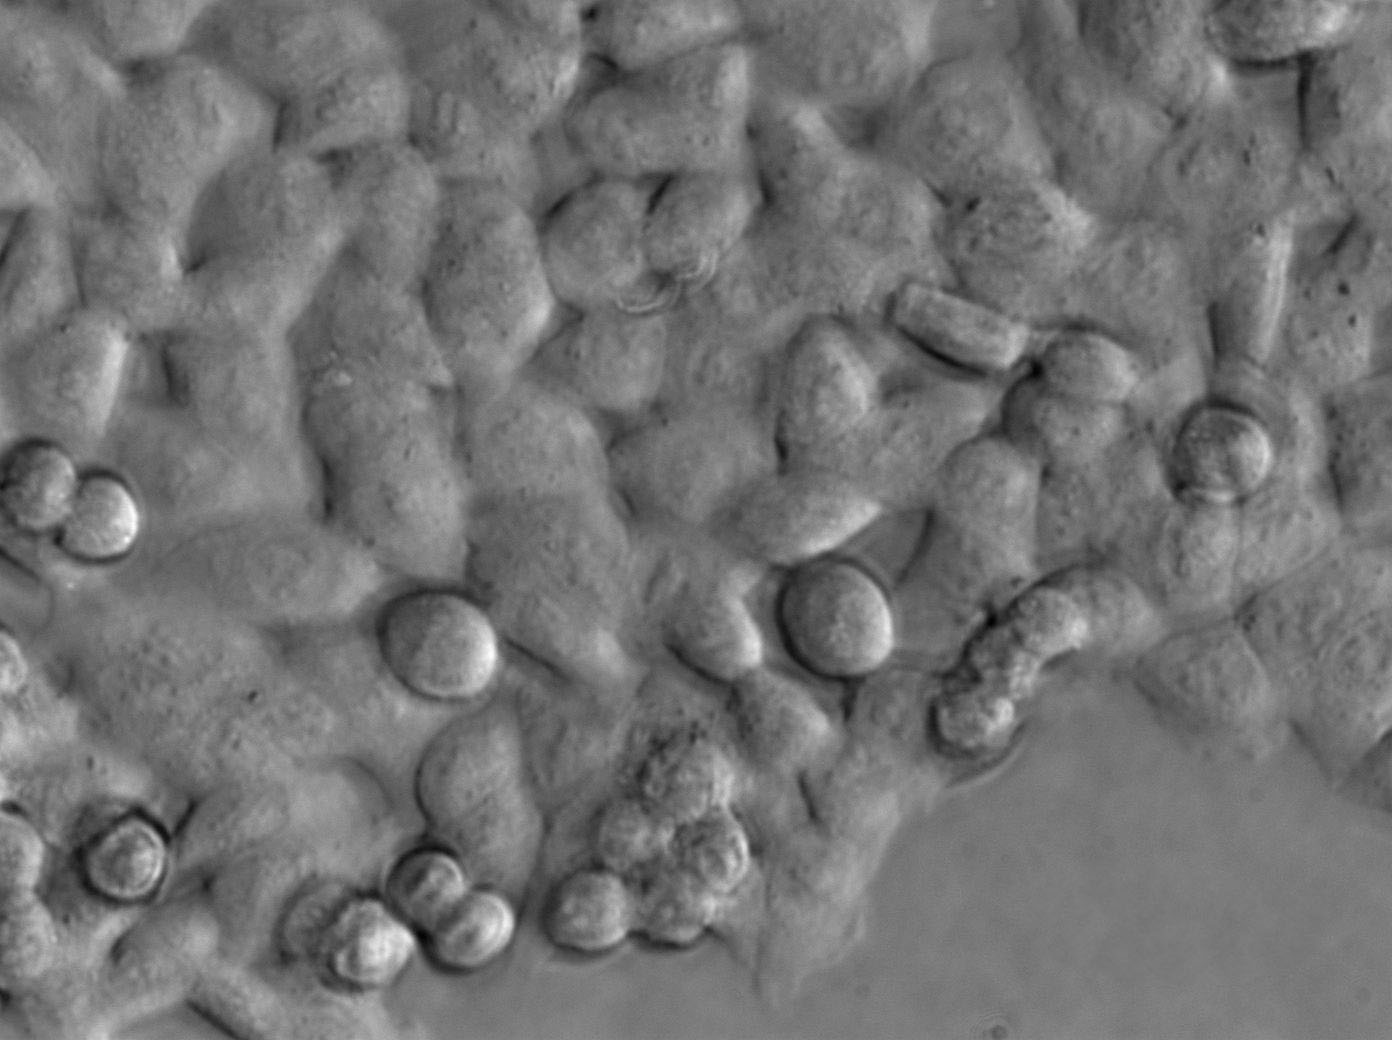

细胞形态:上皮细胞样

细胞生长:贴壁

细胞生长特性:贴壁生长